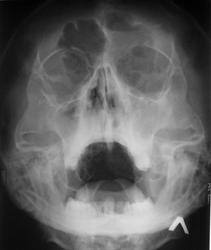

да, признаки пансинуита, но надо обратить внимание на правый сосцевидный отросток, создаётся впечатление, что он частично завуалирован,рекомендовано КТ и укладку по Шуллеру.

Полисинусит. И что то правая лобная пазуха таких больших размеров.....

А левая еще больше.

И с уровнем

Рентгенпризнаки двустороннего гайморита, левостороннего фронтита.

А по случаю - пансинуит, тут глаза болеть могут.....